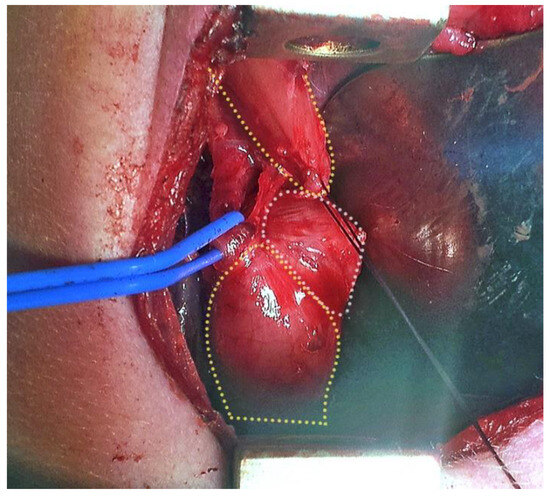

EA associating esophageal duplication cyst: case 1